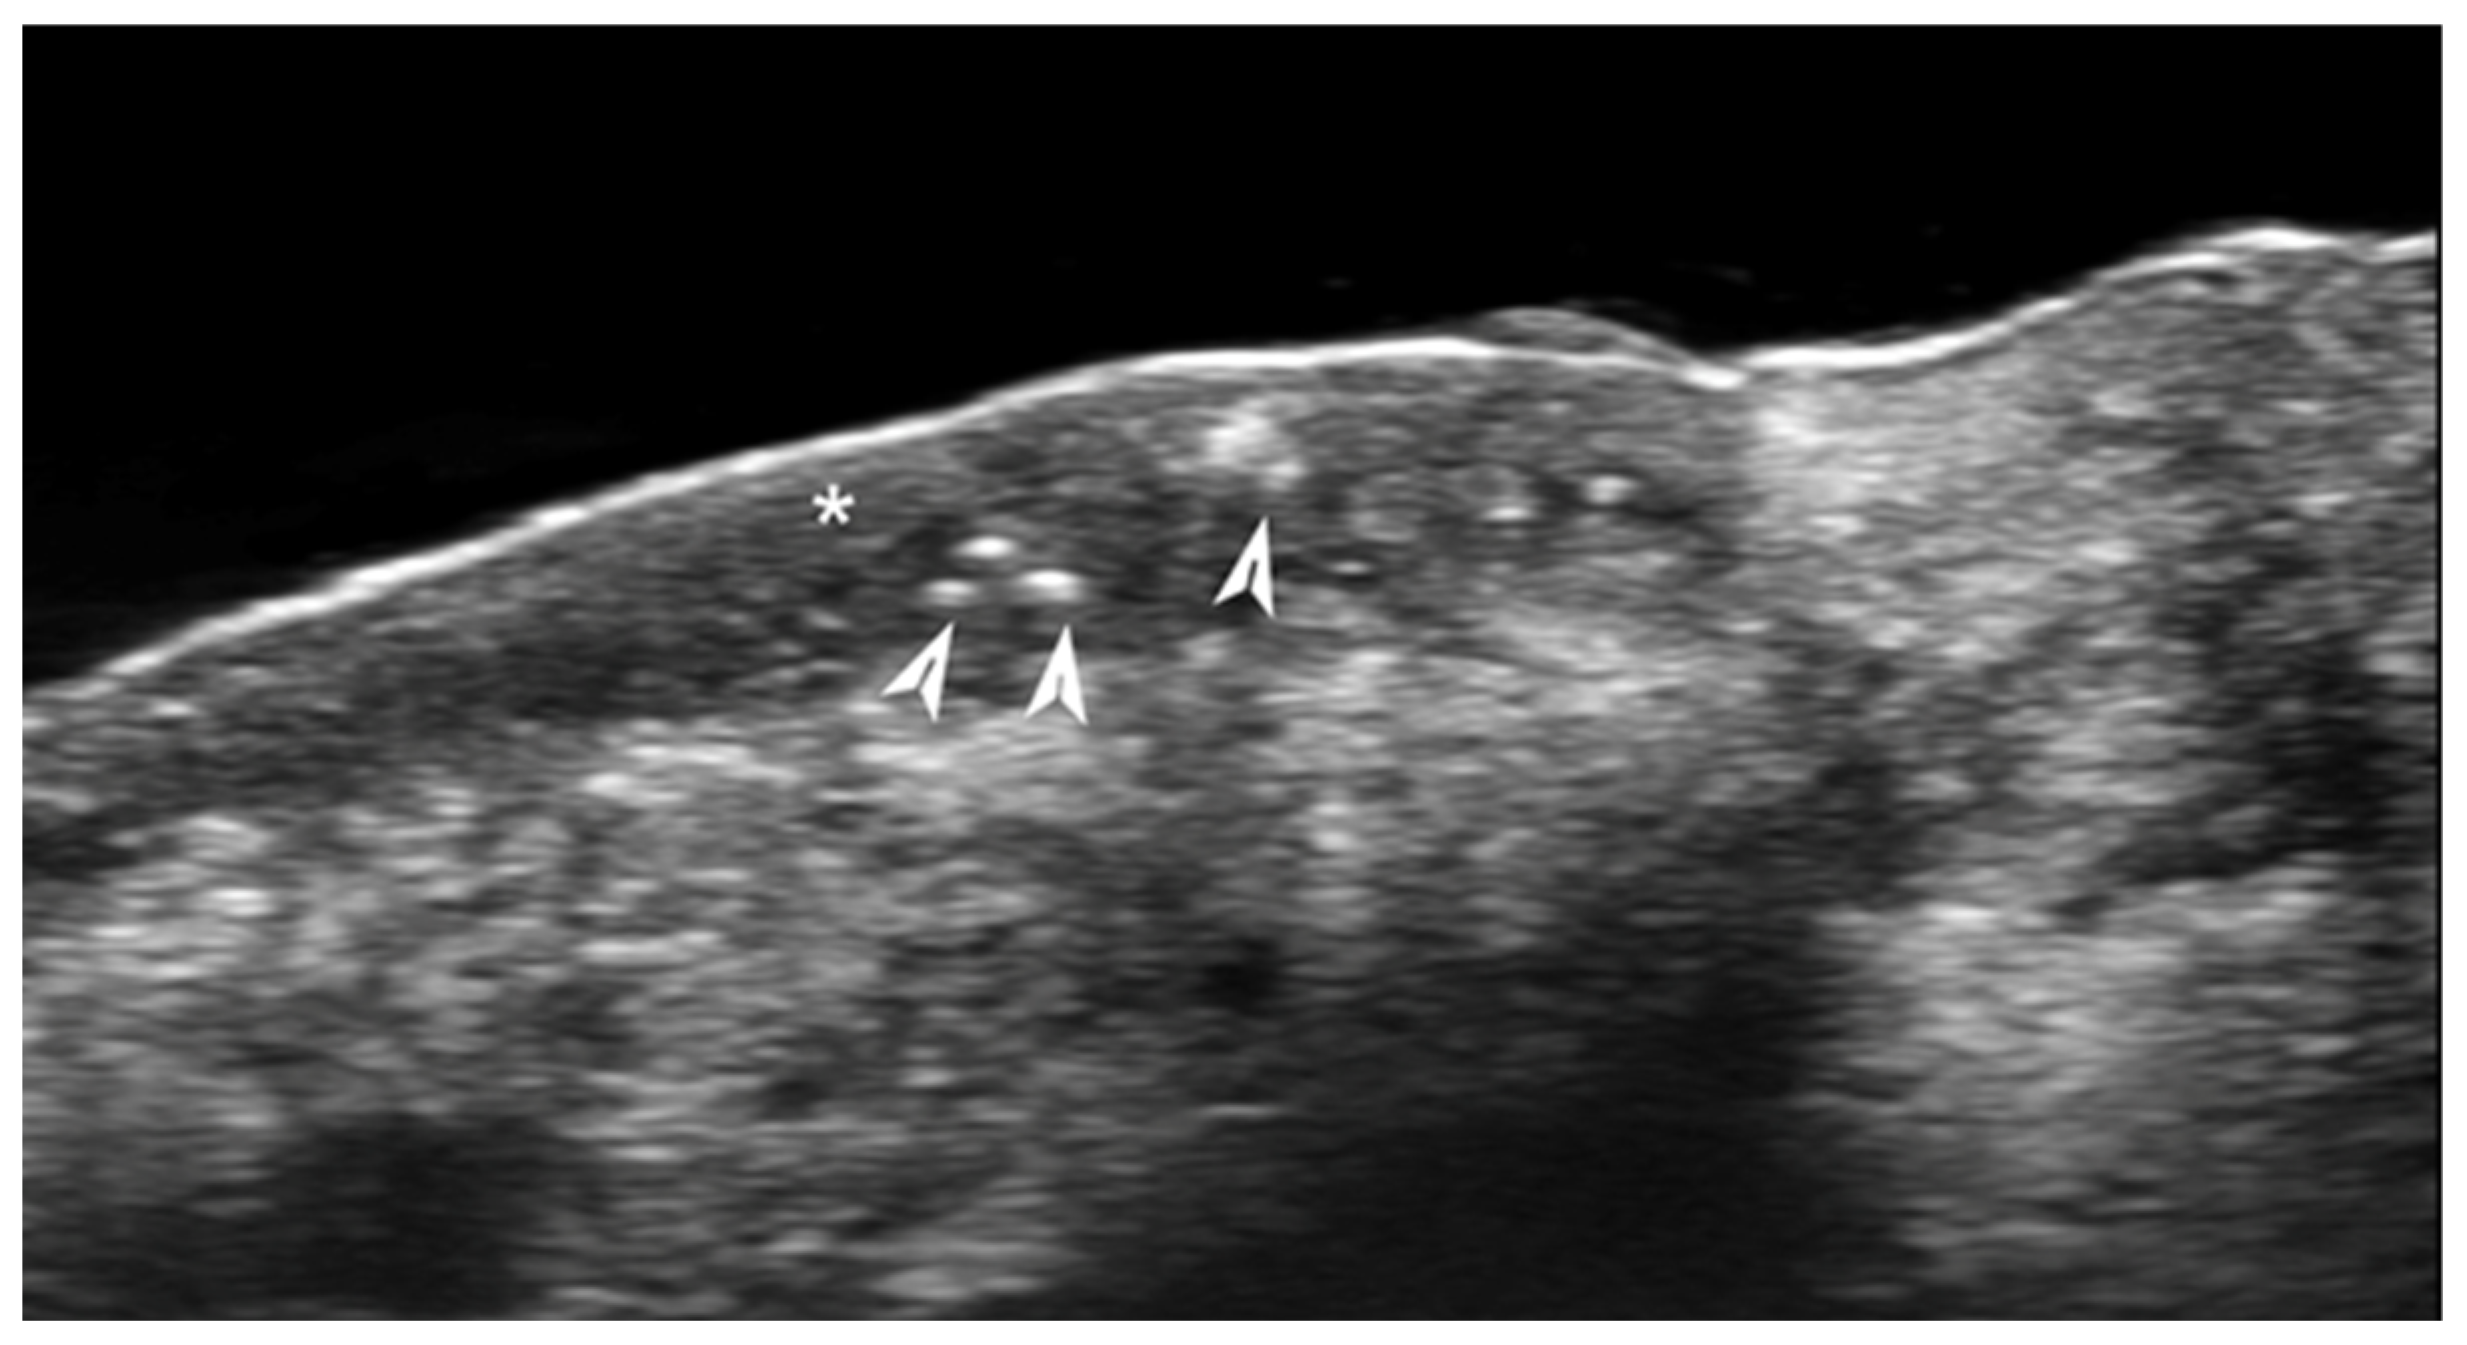

- Kinoshita-Ise, M.; Ohyama, M.; Ramjist, J.M.; Foster, F.S.; Yang, V.X.D.; Sachdeva, M.; Sade, S.; Shear, N.H. Ultra high-frequency ultrasound with seventy-MHz transducer in hair disorders: Development of a novel noninvasive diagnostic methodology. J Dermatol. Sci. 2021, 102, 167–176. [Google Scholar] [CrossRef]